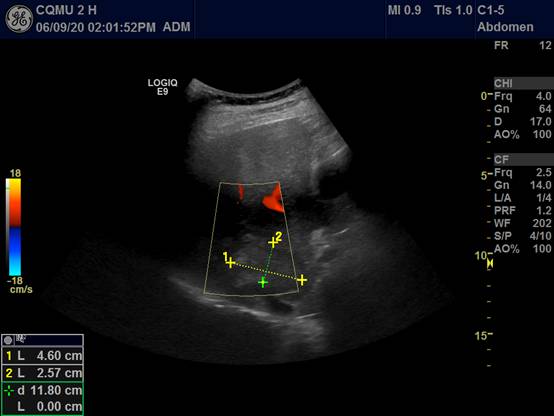

2.超声影像精准引导: